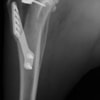

術後写真

手術前後のTPA(脛骨高平部の角度)を測定しています。

約29°から約10°へ矯正されています。

本症例は、走った後に左後肢を挙上していることを主訴に来院されました。触診時に左膝関節のクリック音を聴取、レントゲン検査にて左脛骨の前方変位が認められました。術中に、前十字靱帯の断裂及び内側半月板の損傷、内側の軟部組織の顕著な腫脹を確認。半月板切除、TPLOを実施しました。周囲組織への炎症の波及もあったため回復に時間を要しておりますが、徐々に跛行頻度は減少傾向にあり、現在も経過観察中です。術前に約29°あったTPAは術後に約10°まで矯正されました。